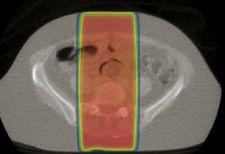

A traditional palliative treatment with two treatment fields aimed from the

TOHCC clinicians have carefully assessed the system as a new tool for palliative care. They have observed highly conformal dose distributions that have reduced radiation dose to surrounding healthy tissues.

“We have found that dose distributions from StatRT are much more conformal than with traditional palliative techniques,” MacPherson said. “This allows for better tissue sparing and, we hope, better tolerance of treatment.”